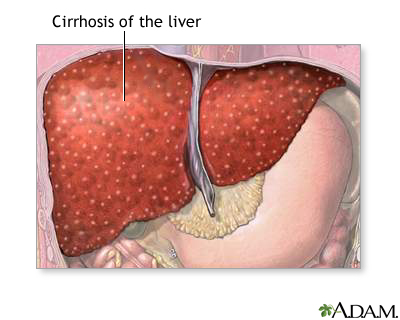

Cirrhosis is a liver disease characterized by permanent scarring of the liver that interferes with its normal functions. Causes include:

Cirrhosis is scarring of the liver and poor liver function. It results from various disorders that damage liver cells over time. Eventually, damage becomes so extensive that the normal structure of the liver is distorted and its function is impaired.

Cirrhosis is the end result of long-term liver damage. Alcohol abuse, and chronic hepatitis B and C, are the leading causes of cirrhosis. Nonalcoholic steatohepatitis (NASH) is also being recognized as a major cause of cirrhosis.

Scarring

The main damage in cirrhosis is triggered by scarring that occurs from inflammation and injuries due to alcohol, viruses like hepatitis B and C, or other damage. The scar tissue and other changes in liver cells gradually replace healthy liver tissue and act like small dams to alter the flow of blood and bile in and out of the liver. The initial stage of light to moderate scarring in the liver is calledfibrosis

. As the scarring becomes more severe and extensive, cirrhosis occurs.Altered Blood and Bile Flow